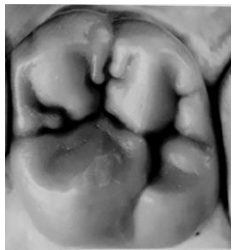

RIQUIERI, Hilton. Anatomia e Escultura Dental. Coleção APDESP. Ed.Napoleão.

Assinale a opção que indica o elemento dentário que corresponde à imagem acima.